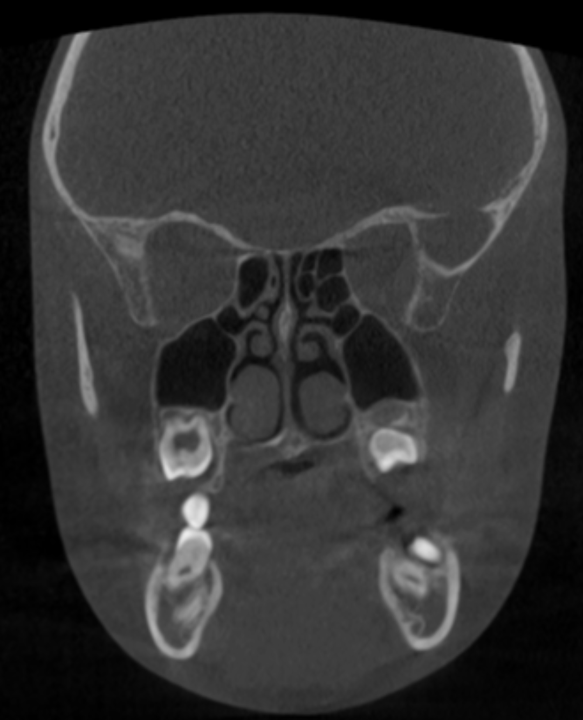

BENEFICIOS EN DIAGNÓSTICO DENTAL

- Ortodoncia avanzada

- Posición exacta de dientes retenidos

- Reabsorciones radiculares

- Relación con corticales óseas

- ATM (articulación temporomandibular)

- Cóndilo

- Fosa glenoidea

- Asimetrías

👉 Muy útil en pacientes con dolor o disfunción

- Adenoides (muy importante en niños)

- Tamaño real

- Relación con vía aérea

- Grado de obstrucción

Mucho más preciso que radiografía lateral